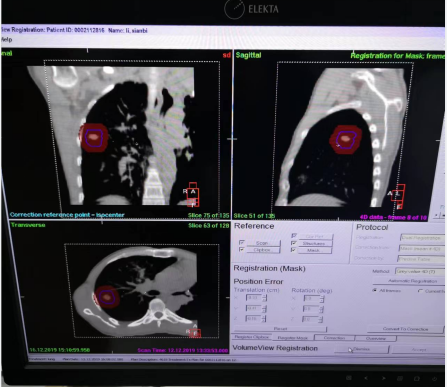

4. 加速器上治疗时,确保患者体位和ABC的连接方式与扫描CT时一致。患者一只手握住门控开关,戴一副折射眼镜(患者在治疗时可以同步看到电脑系统的提示内容),在达到当时训练时设置的吸气阈值时开始屏气,加速器出束前先进行影像验证(CBCT)确保体位的准确性。

5. 在治疗时,先吸气至阈值后治疗师操作加速器开始出束,一个野治疗完毕后,患者恢复呼吸,准备第二次屏气治疗,周而复始,直到治疗结束(患者屏气无法坚持到一个野出束完毕,可以自行松开手中阀门,加速器连锁会停止出束)。